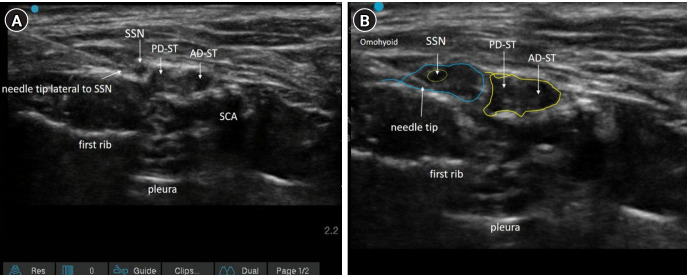

Methods: We injected 5 ml of 0.1% methylene blue dye into the proximal portion of the suprascapular nerve (infra-omohyoid in the posterior triangle) in 12 neck specimens from six cadavers. Following meticulous dissection, we assessed the spread of the dye along the brachial plexus to the nerve roots and traced the phrenic nerve for staining.